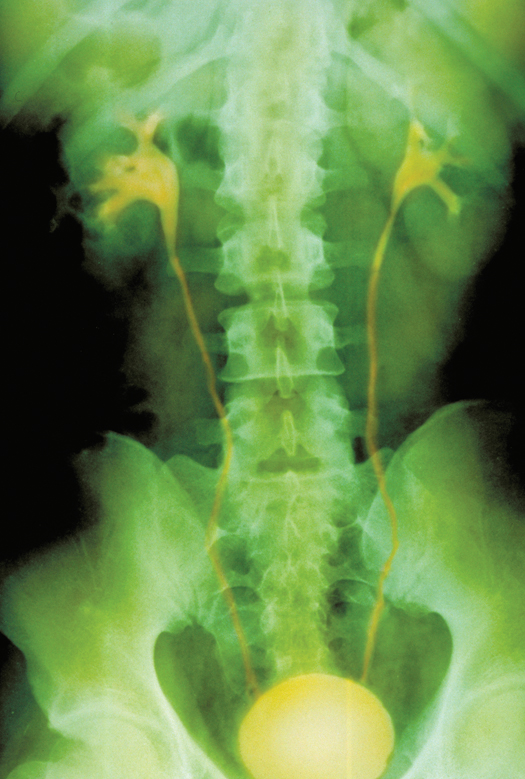

Color enhanced normal intravenous pyelogram (IVP), a x-ray which displays the drainage of urine from the kidneys through the ureters towards the bladder. Seen here are the kidneys, ureters, and rounded thick walled bladder in a 22 year old male. BIOPHOTO ASSOCIATES